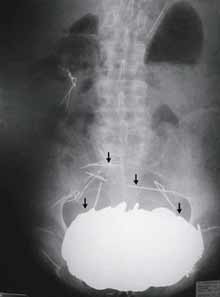

An X-Ray, made of the stomach of a 62-year-old man who came to the emergency room of Cholet General Hospital in western France in 2002. [AP Photo]

Still, doctors were awed when they took an X-ray. They discovered an enormous opaque mass in his stomach that turned out to weigh 12 pounds — as much as some bowling balls. It was so heavy it had forced his stomach down between his hips.

A few details of the Frenchman's case were presented Jan. 1 along with the X-ray — but no explanation of the stomach mass — as a challenge to New England Journal of Medicine readers in a fixture called "A Medical Mystery."